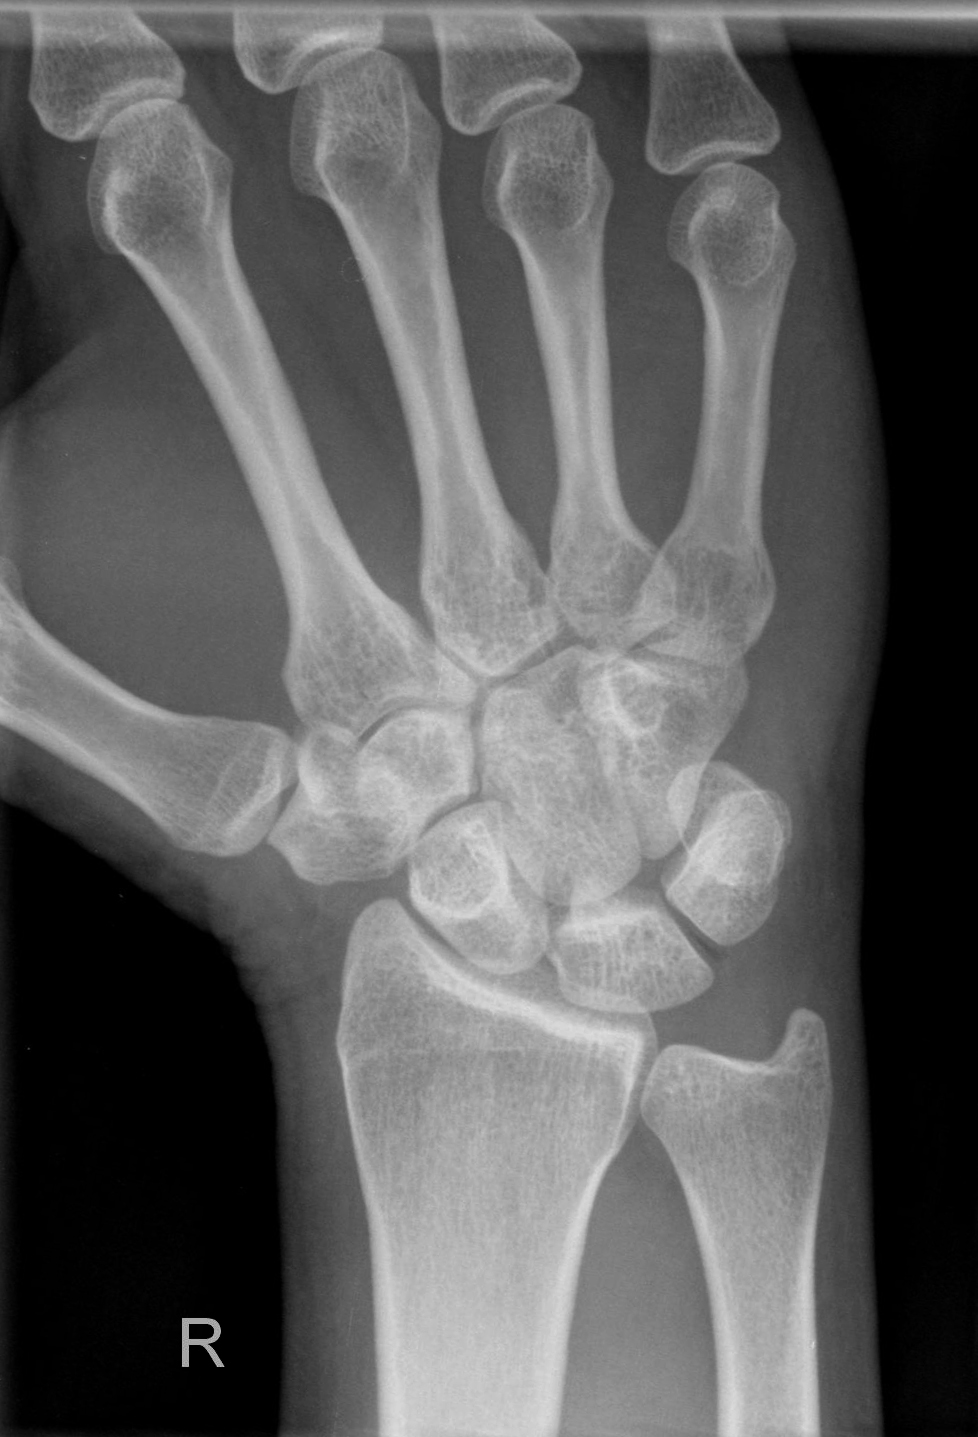

Hand d.v. (dorso-volar)

Indikation

Frakturen, entzündliche (Arthrose) und degenerative Veränderungen (Arthritis), chronische Polyarthritis (Rheuma)

Lagerung

Patient sitzt seitlich zum Tisch, Beine befinden sich neben Tisch abgewinkelter Unterarm und die Handfläche liegen auf.

Zentralstrahl

senkrecht auf Objektmitte

Einblendung

proximal einschließlich Proc. styloideus radii und ulnae

Anmerkung

Übersichtsdarstellung des Skeletts bei Frakturen, Arthrosis und Deformierung der Gelenke, sowie chronischer Polyarthritis (Rheuma).

Fragestellungsabhängige Einblendung mögl. z. B. Mittelhand

Qualitätskriterien

vollständige Darstellung der ganzen Hand inklusive Handgelenk, Buchstabe